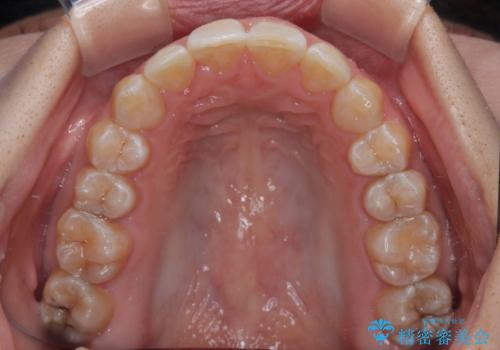

前歯のデコボコをインビザライン矯正で綺麗に改善

- 上下前歯のデコボコを気にして来院された患者様です。

全体的に叢生は軽度であったため、インビザラインにて矯正治療を行うこととしました。

気になる段差を納得いくまで改善させたため、治療期間は長くなりましたが、綺麗な仕上がりとなりました。